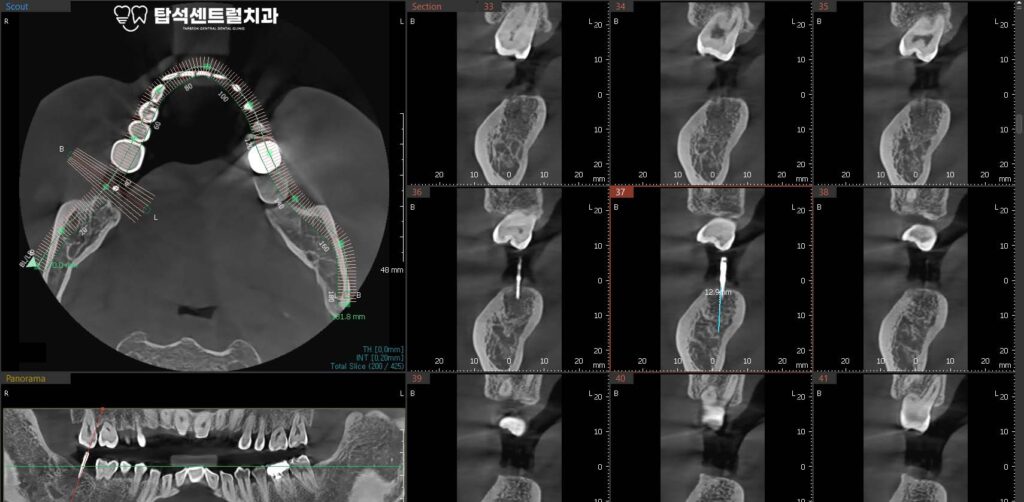

이번 의정부 치과 에서 소개해드린

케이스의 경우에는, 아래턱에

임플란트를 식립할 예정입니다.

잇몸뼈의 상태를 확인한 모습입니다.

잇몸 뼈가 남아 있는 양에 따라,

뼈이식의 필요 유무가 정해집니다.